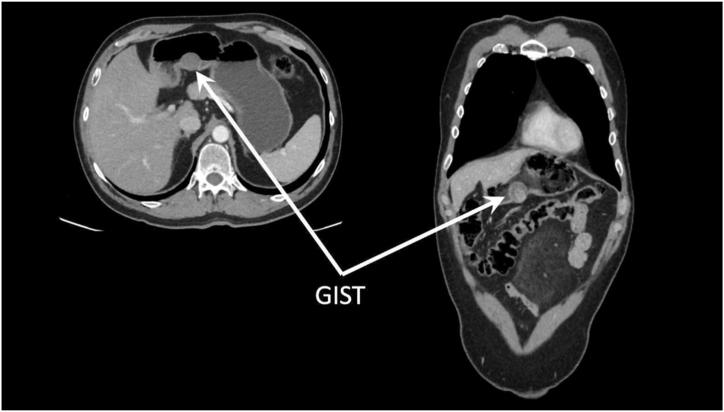

Gastrointestinal stromal tumors, the most prevalent mesenchymal tumors (80 %) of the gastrointestinal tract, comprise less than 1 % of all gastrointestinal neoplasms and about 5 % of all sarcomas. Despite their rarity, Gastrointestinal stromal tumors present diverse clinical manifestations, anatomic locations, histological subtypes, and prognostic outcomes.

This scoping review comprehensively explores the epidemiology, clinical characteristics, diagnostic and prognostic modalities, as well as new therapeutic options for Gastrointestinal stromal tumors.